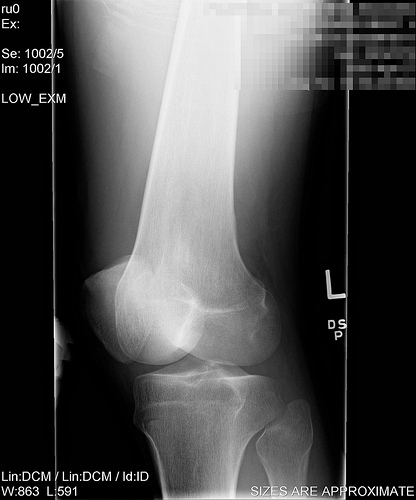

Summer is here and many of my clients are preparing for the Half Marathon September 12, 2010 and the Chicago Marathon, October 10, 2010. Training is a good time to think about proper joint care. Recent research indicates that running can help maintain the health of your joints by providing your body with proper blood flow, oxygen and stimulation of healthy bone and connective tissue. However, over the years, many runners sustain injuries that can lead to arthritis. And if a runner has poor form or a gait imbalance (runs on a pronated foot, for example) this can also lead to uneven wear and tear on joints.

• Do NOT run when you are injured. If you feel a sharp pain in your knee, ankle, hip or muscle when you run, stop and rest. And get it checked out by your doctor to avoid further injury or complications.